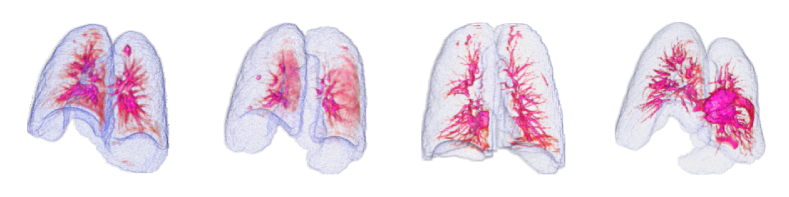

By using the internal clinical dataset from SMC of pneumonia and tuberculosis cases, we experimentally verified the superiority of the proposed VMPR-UAD through various comparative experiments. We also provide quantitative results and 3D abnormal (lesion) localization/visualization results of VMPR-UAD using the internal dataset for pneumonia and tuberculosis in the Supplementary Material to illustrate the superiority of anomaly localization by VMPR-UAD.

3.4.1 Performance of VMPR-UAD and SL method

The proposed VMPR-UAD only requires data from healthy subjects for network training. To compare the VMPR-UAD with an SL method that requires training data from both healthy subjects and patients showing anomalies, the SL method was trained as follows. We set the number of training samples to the maximum possible, with the ratio of normal to abnormal cases being 1:1, and fivefold Monte Carlo validation was adopted during SL training. We randomly selected 450 normal, 350 pneumonia, and 100 tuberculosis cases for training. For pneumonia detection using the SL method, 350 of the remaining stacks from healthy subjects were randomly selected along with 350 stacks showing pneumonia. For tuberculosis detection, 100 stacks from healthy subjects were randomly selected along with the 100 stacks showing tuberculosis. For detection of both diseases, 450 stacks from healthy subjects were randomly selected along with the 350 and 100 stacks showing pneumonia and tuberculosis, respectively. For the SL network, we adopted a 3D convolutional neural network, 3D-ResNet18 [40], with the 3D stack of original CT slices as its input. The results of comparing the SL method with the proposed VMPR-UAD are listed in Table C and shown in Fig. G. The proposed VMPR-UAD shows higher performance in anomaly detection by improving the AUC by more than 10%, despite only using data from healthy subjects for training. This result confirms the superiority and convenience of our proposal over an SL-based diagnosis, especially when the training data of the target disease are insufficient or difficult to distinguish and annotate.